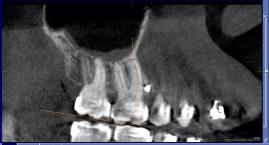

The axial inclination of the maxillary first permanent molar was measured using the molar occlusal plane as a reference. This was evaluated using the tangential window on the panoramic view which was kept in the region of the maxillary molars. As the DICOM images were viewed from the right to the left side in the region of the molars, the maxillary palate was not visible in the posterior region and hence the palatal plane could not be used as a reference plane. However, the entire length of the maxillary first and second permanent molars was visible in only one or two images. One definitive image was selected and the molar occlusal plane was drawn horizontally from the distal cusp of the maxillary second permanent molar to the mesial cusp of the maxillary first permanent molar. The long axis of the tooth was drawn along the mesiobuccal cusp to the mesiobuccal root apex of the maxillary first permanent molar (Figure 2). The angle between the molar occlusal plane and the long axis of the molar was recorded separately on both the right and left side.

Shows the measurement of the inclination of the maxillary first permanent molar using the molar occlusal plane as reference on the CBCT scan.